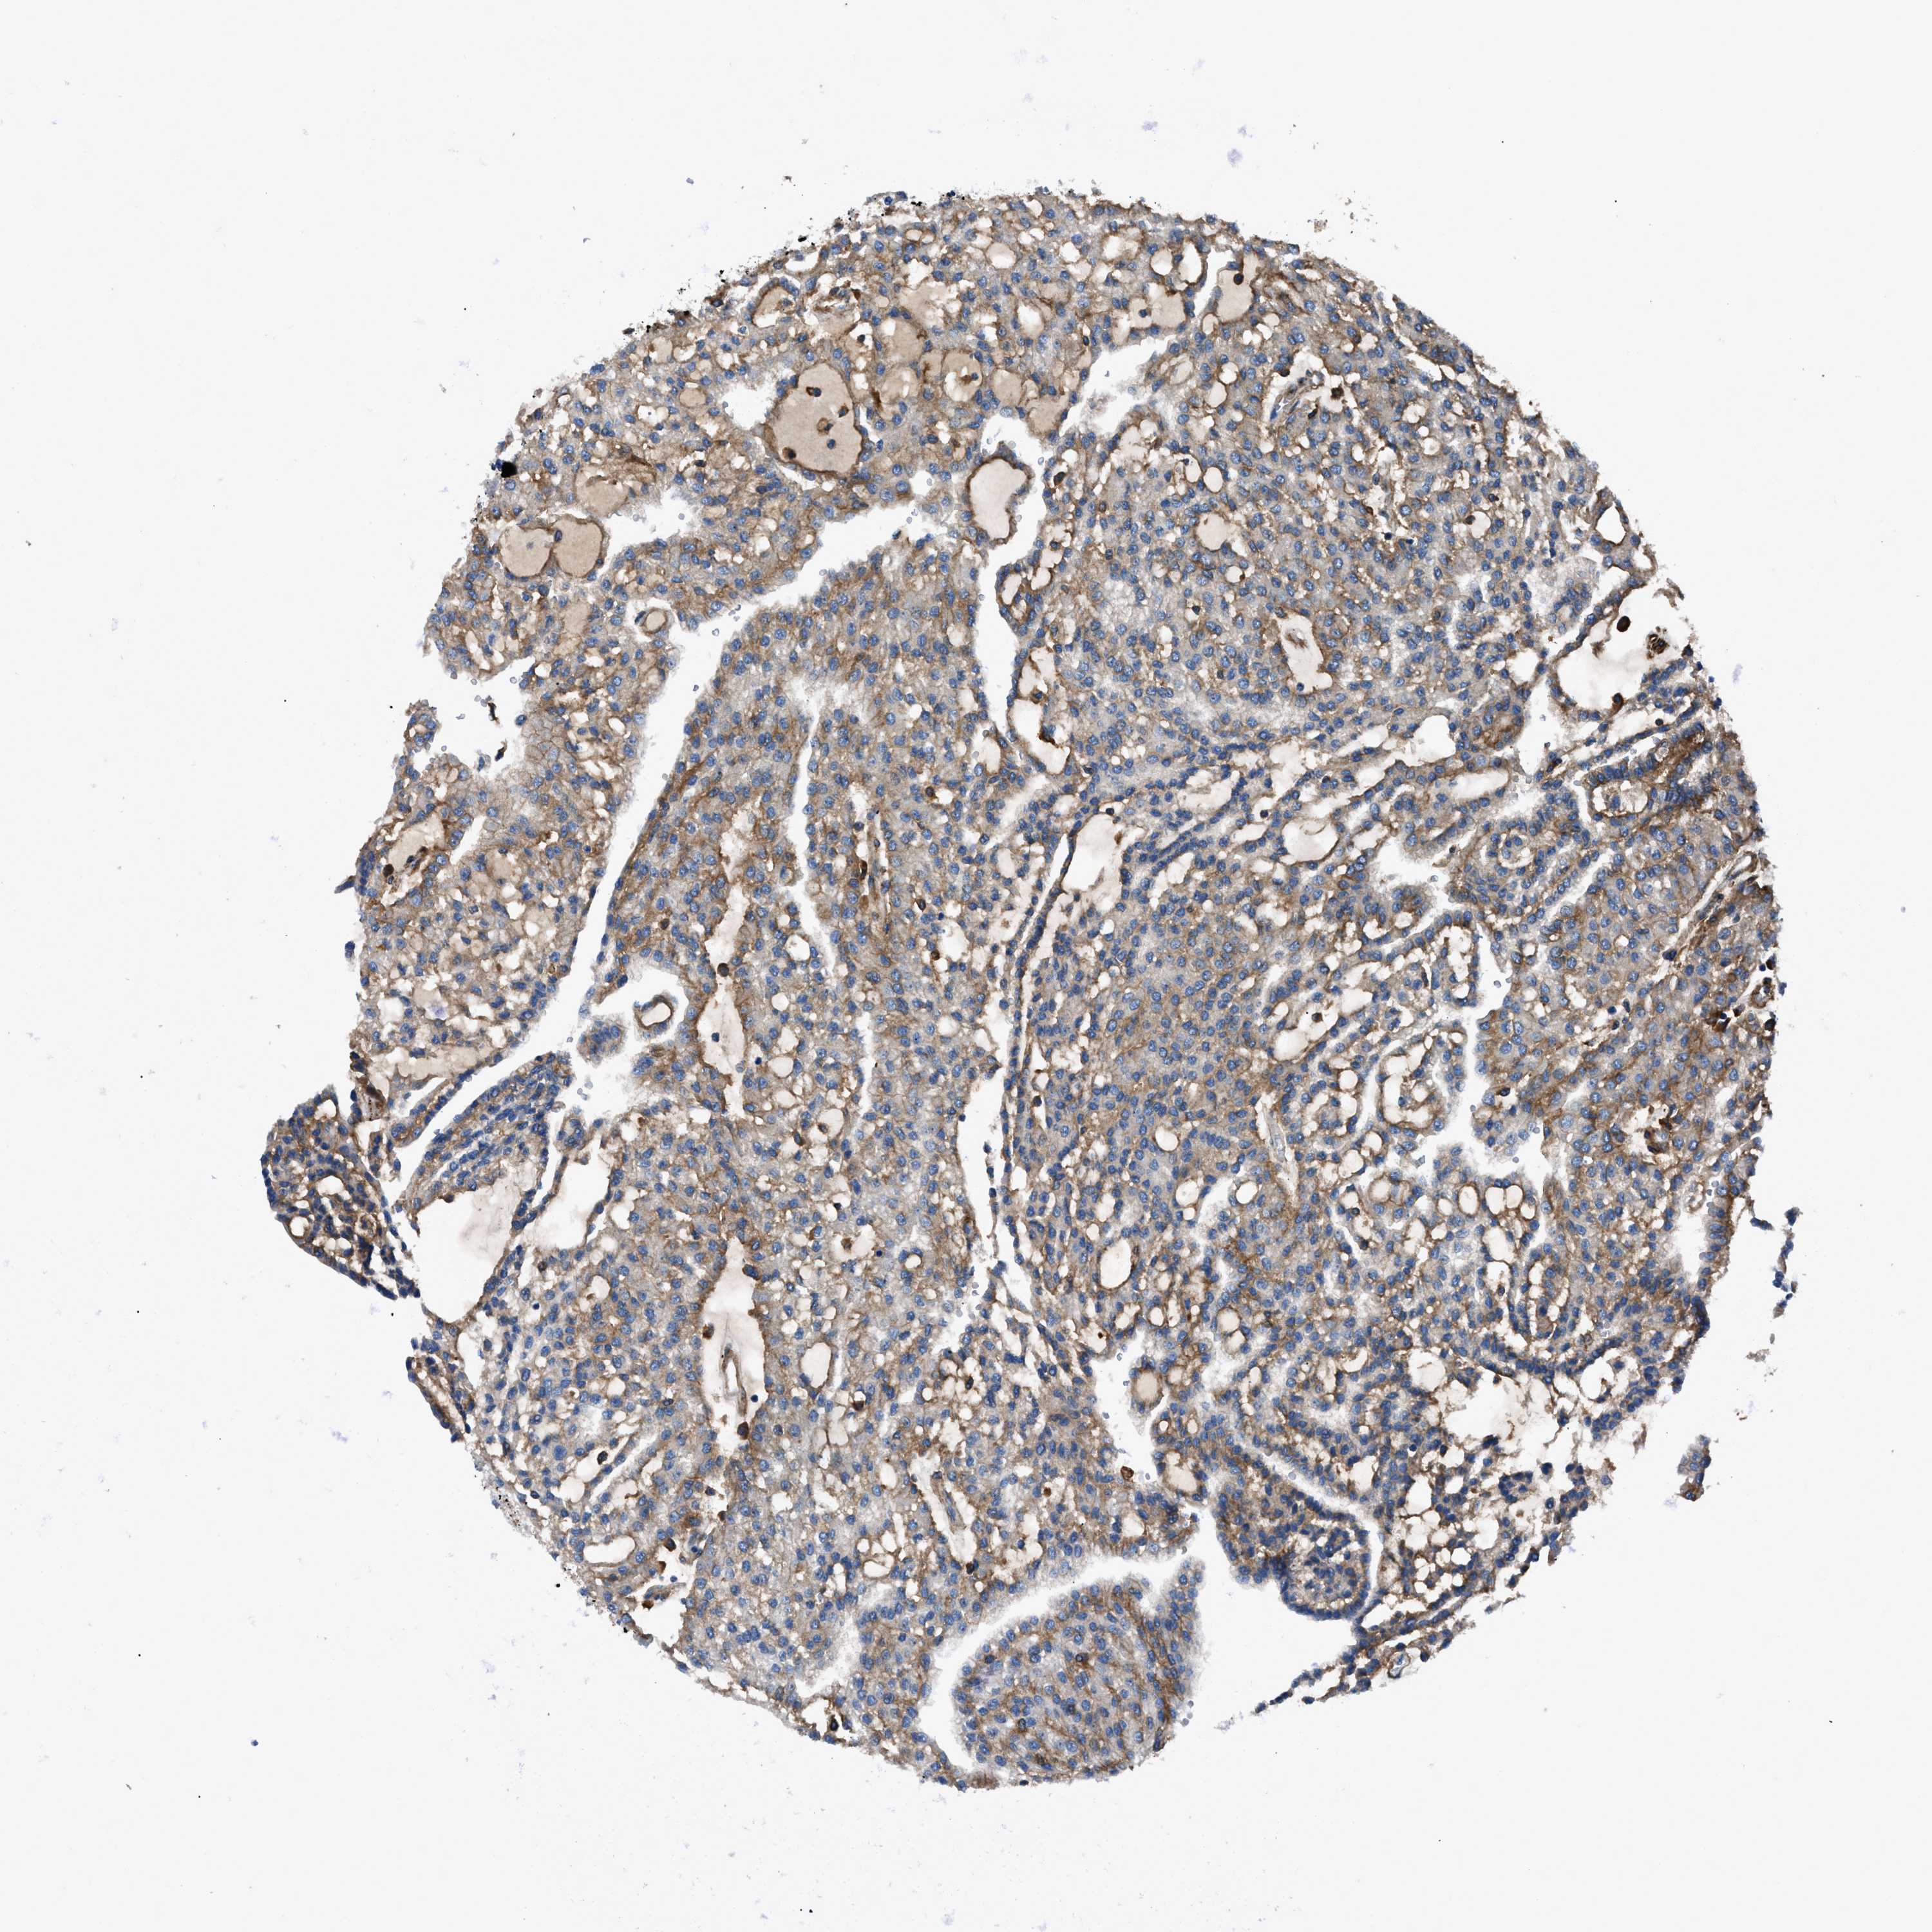

KIDNEY RENAL CLEAR CELL CARCINOMA (VALIDATION) - Interactive survival scatter ploti

The Survival Scatter plot shows the clinical status (i.e. dead or alive) for all individuals in the patient cohort, based on the same data that underlies the corresponding Kaplan-Meier plots. Patients that are alive at last time for follow-up are shown in blue and patients who have died during the study are shown in red.

The x-axis shows the expression levels (FPKM) of the investigated gene in the tumor tissue at the time of diagnosis. The y-axis shows the follow-up time after diagnosis (years). Both axes are complimented with kernel density curves demonstrating the data density over the axes. The top density plot shows the expression levels (FPKM) distribution among dead (red) and alive patients (blue). The right density plot shows the data density of the survived years of dead patients with high and low expression levels respectively, stratified using the cutoff indicated by the vertical dashed line through the Survival Scatter plot. This cutoff is automatically defined based on the FPKM cutoff that minimizes the p-score. The cutoff can be changed by dragging the vertical line or by entering a cutoff value in the square labeled "Current cut-off".

Under the Survival Scatter plot the p-score landscape (black curve; left axis) is shown together with dead median separation (red curve; right axis). Dead median separation is the difference in median mRNA expression between patients who have died with high and low expression, respectively. It is calculated as follows: median FPKM expression of dead patients with high expression - median FPKM expression of dead patients with low expression. This is intended to aid the user in visually exploring custom cutoffs and the associated p-scores and dead median separation.

Individual patient data is displayed and can be filtered by clicking on one or more of the category buttons on the top of the page. Categories describing expression level and patient information include: high, low, alive, dead, female, male and tumor stages. The scale of the x-axis can be toggled between linear and log-scale by clicking on the "x log" button. Mouse-over function shows TCGA ID, patient information and mRNA expression (FPKM) for each patient.

& Survival analysisi

Kaplan-Meier plots summarize results from analysis of correlation between mRNA expression level and patient survival. Patients were divided based on level of expression into one of the two groups "low" (under cut off) or "high" (over cut off). X-axis shows time for survival (years) and y-axis shows the probability of survival, where 1.0 corresponds to 100 percent.

CD276 is not prognostic in Kidney Renal Clear Cell Carcinoma (validation)

Best expression cut offi

Based on the FPKM value of each gene, patients were classified into two groups and association between prognosis (survival) and gene expression (FPKM) was examined. The best expression cut-off refers the FPKM value that yields maximal difference with regard to survival between the two groups at the lowest log-rank P-value. Best expression cut-off was selected based on survival analysis .

When clicking on this number, the vertical dashed line indicating cut-off, the interactive survival plot, and the Kaplan-Meier curve will be adjusted to show results based on the best expression cut-off.

: 20.56

P scorei

Log-rank P value for Kaplan-Meier plot showing results from analysis of correlation between mRNA expression level and patient survival.

N/A

TCGA RNA samplesi

RNA-seq data is reported as average FPKM (number Fragments Per Kilobase of exon per Million reads), generated by the The Cancer Genome Atlas (TCGA) .

Normal distribution across the dataset is visualized with box plots, shown as median and 25th and 75th percentiles. Points are displayed as outliers if they are above or below 1.5 times the interquartile range. FPKM values of the individual samples are presented next to the box plot.

Average pTPM 32.6

Number of samples 100